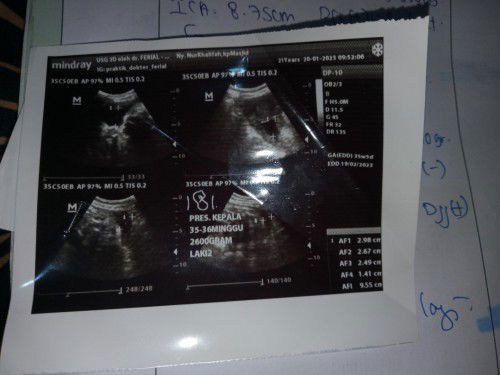

Barangkali disini ada yang sama ky aku bun. Usia kandungan aku 32minggu hpl insyaallah tanggal 19feb

Barangkali disini ada yang sama ky aku bun. Usia kandungan aku 32minggu hpl insyaallah tanggal 19februari. Tapi aku lagi khawatir Bun,takut asi ku gak keluar karena payudara aku kecil banget 😭 kira2 ada yang sama gak ky aku payudaranya kecil. Mau minum pelancar ASI kira2 yang bagus apa ya Bun?😓🙏#seriusnanya #bantusharing